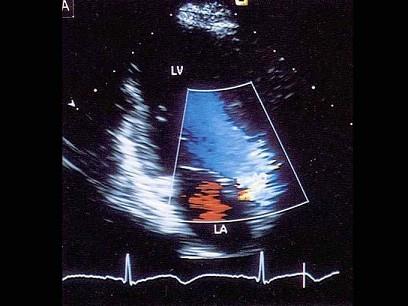

该图蓝色血流信号表示?(?)A.动脉血B.静脉血C.血流方向背离探头D.血流方向朝向探头E.以上均不是

问题 该图蓝色血流信号表示?(?)

选项 A.动脉血 B.静脉血 C.血流方向背离探头 D.血流方向朝向探头 E.以上均不是

答案 C